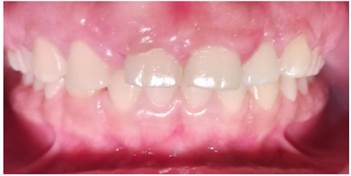

Figura 3. Imágenes Intrabucales

Imagen (a) frente (b) perfil derecho (c) perfil izquierdo.

Las fotografías intrabucales son de gran ayuda para el diagnóstico de patologías en los pacientes, son una herramienta útil y adicional que aporta información valiosa para el profesional de la odontología, aporta registros clínicos, en este caso la cirugía bucal.